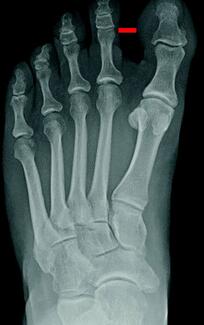

This article presents a novel technique for temporary fixation for the distal Chevron osteotomy for hallux valgus. The authors theorize that the use of this “goalpost” technique produces a simple, stable, and reproducible outcome that...

Does hallux varus present to podiatric offices more than we realize? Here the author outlines his experience over 30 years and contends that this condition can appear even under unexpected circumstances.